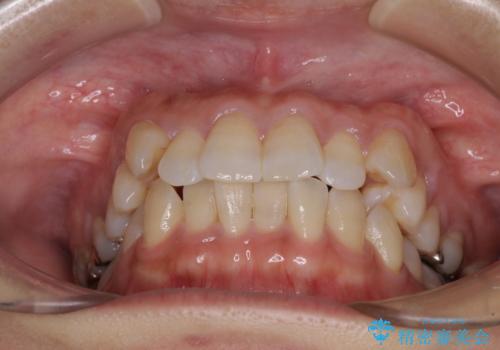

気になる八重歯 ワイヤー装置での非抜歯矯正

- 上顎の八重歯と全体的なデコボコを気にして来院された患者様です。

口元の突出感はなかったため非抜歯矯正での対応となりますが、八重歯を改善する際に上顎前歯が前突する可能性があったため、上顎臼歯部にアンカースクリューを使用して、歯列が前方に転位しないようにすることとしました。

ワイヤー矯正でもインビザラインでも対応可能でしたが、上顎歯列が前方位であるときには、ワイヤー矯正の方がより良い仕上がりとなる可能性が高いため、ワイヤー矯正をおすすめいたしました。